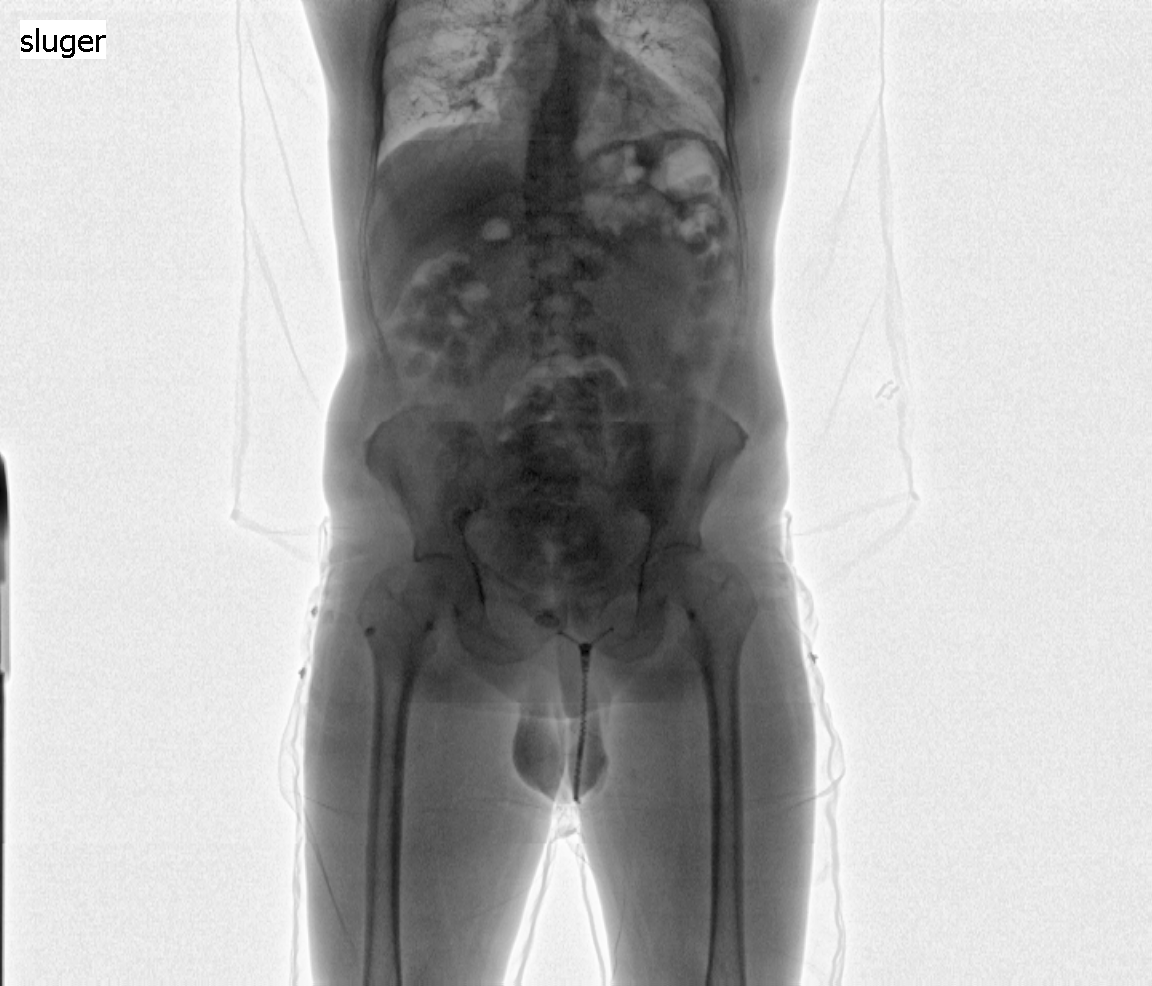

Selve scanningen foregår ved, at personen bliver placeret, fuldt påklædt, på en platform i bilen, som på få sekunder kører forbi scanneren. Scanneren tager to røntgenbilleder: et af hele kroppen og et kun af torso. Billederne overføres straks til scanneroperatøren, der sidder i bilens operatørrum. Hvis operatøren ser, at der er gemt uidentificeret indhold i kroppen, bliver den mistænkte person overgivet til politiet, der vil stå for den videre håndtering.

Scanningsbillede 2 - person med 75 kugler kokain med samlet vægt på ca. 1 kg.